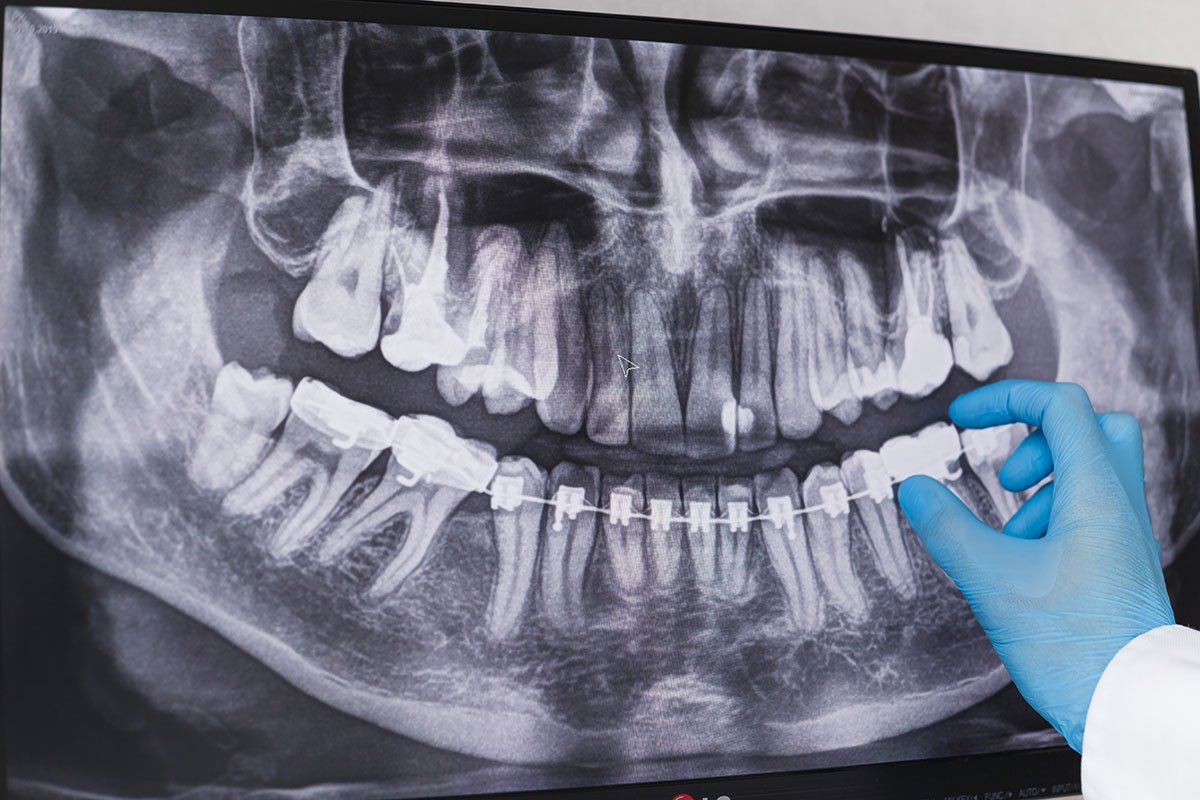

La ortopantomografía, también llamada radiografía panorámica dental, es una radiografía que permite explorar la estructura dental, ofreciendo una imagen completa de toda la estructura dental, bucal y facial.

Es bastante útil para detectar anomalías que generan problemas dentales, en los maxilares o la mandíbula y su articulación. Este método es muy importante en la odontología, ya que ofrece una imagen bastante completa de la boca.

Se logra que la imagen se vea tridimensional gracias a la superposición de cada plano bidimensional para formar la imagen. Es decir, cada plano bidimensional de cada área bucal, se superpone para obtener una imagen en tres dimensiones.

De esta forma es mucho más fácil determinar la existencia de algún tipo de problema, incluso los relacionados con la articulación temporomandibular. Es tan completo y preciso el diagnóstico que puede determinarse la existencia de caries y otros problemas dentales. Los especialistas de la clínica dental Acacias, recomendamos realizar este examen radiológico una vez al año.

De esta manera en un corto tiempo, el especialista puede determinar los problemas que pueda tener el paciente. Las imágenes se estudian en una pantalla donde aparece la imagen panorámica de la cavidad oral del individuo.